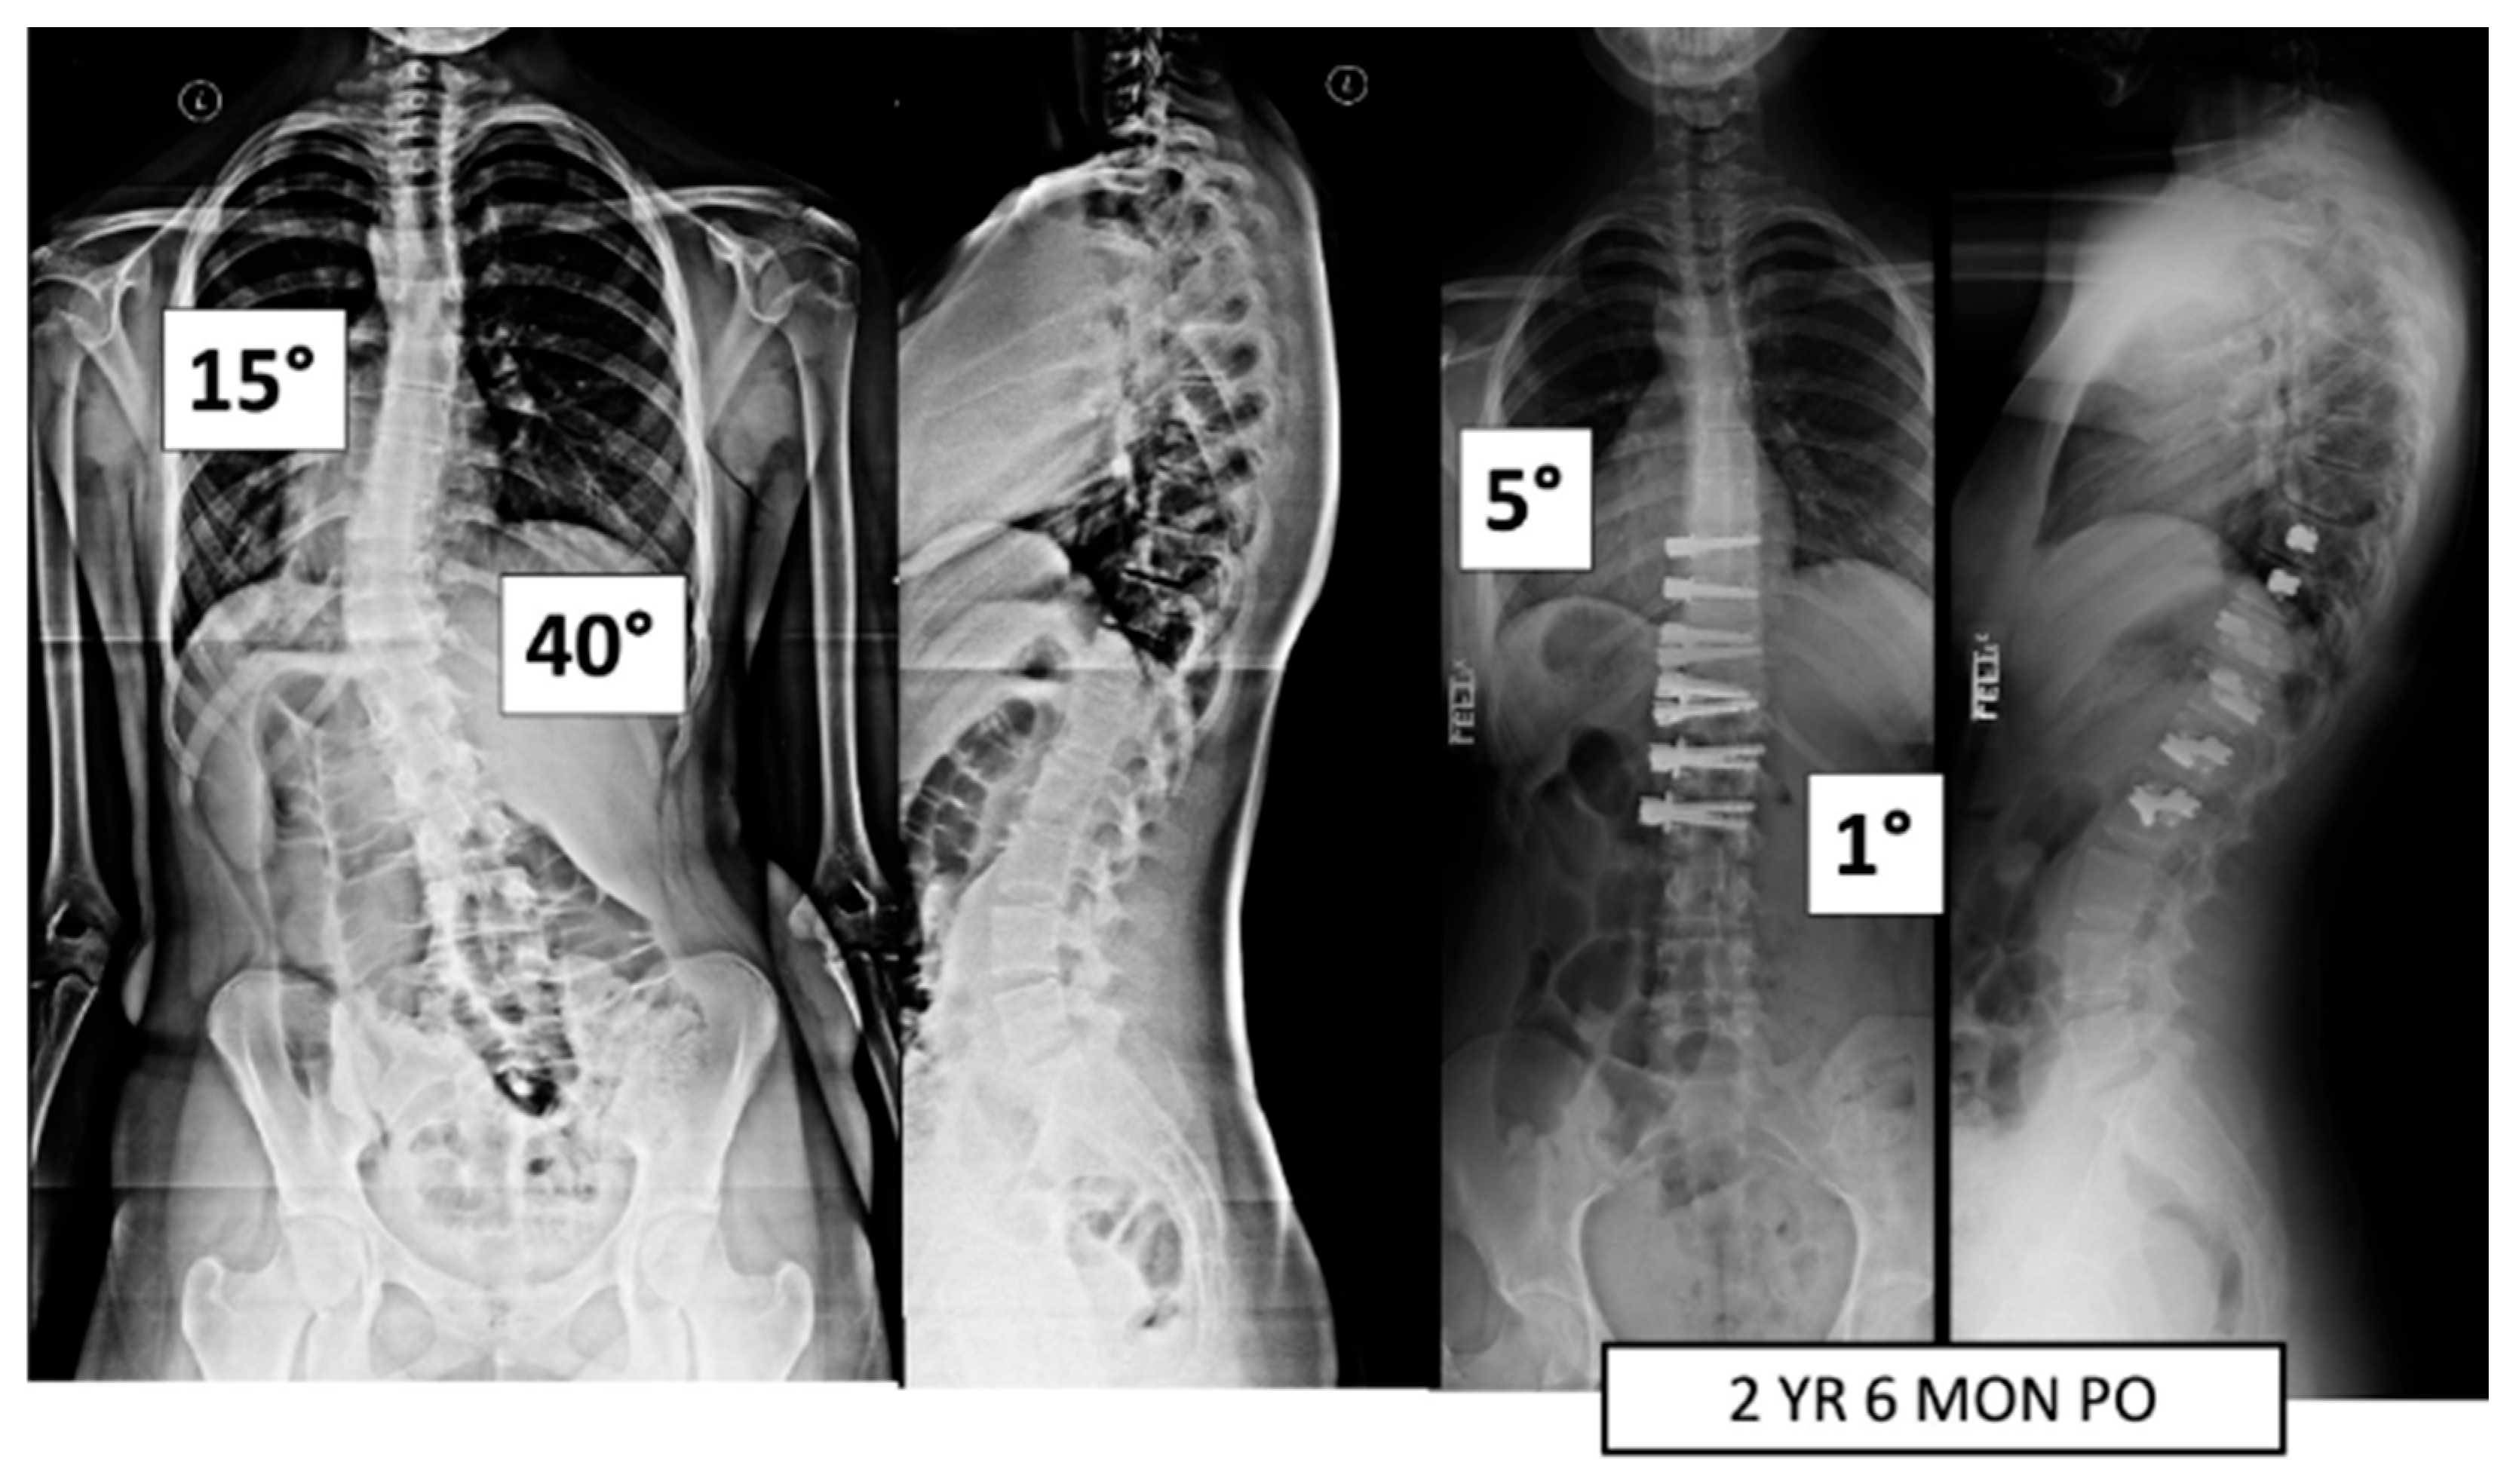

Figure 1.

This is a 15-year-old male treated with bilateral VBT instrumentation. At 5 years and 4 months post operation, he has returned to all activities.

Figure 2.

This is a 15-year-old female treated with lumbar VBT. At 2 years and 6 months post operation, she has resumed all activities with no complications.